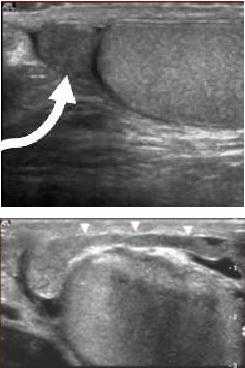

Орхит и эпидидимит - воспаление яичка или его придатка, нередко вызывают формирование реактивного гидроцеле. Кроме увеличения мошонки орхит или эпидидимит может сопровождаться болезненностью мошонки, а также температурой, ознобом дизурией и др. При эпидидимите придаток яичка увеличен в размере и имеет гипоэхогенную структуру. Доплер-УЗИ выявляет усиленный кровоток в области придатка. При орхите яичко на УЗ-изображении имеет гетерогенную структуру.

На рисунках виден увеличенный гипоэхогенный придаток яичка с усиленным кровотоком и небольшого размера реактивное гидроцеле.

На данном рисунке представлено яичко, имеющее негомогенную структуру, и гидроцеле небольшого размера. Такие результаты УЗИ помогают поставить диагноз орхита, сопровождающегося формированием реактивного гидроцеле.

Перекрут яичка - неотложное урологическое состояние, требующее немедленного хирургического лечения. Перекрут яичка сопровождается возникновением острой боли в области мошонки, ее увеличением, тошнотой и рвотой. Так как яичко свободно лежит в мошонке оно легко закручивается вокруг своей оси, что приводит к перекручиванию семенного канатика и нарушению тока крови по его сосудам.

Во время ультразвукового исследования с доплером при перекруте яичка определяется нарушенное кровоснабжение яичка, сопровождающееся формированием реактивного гидроцеле, как показано на рисунке.